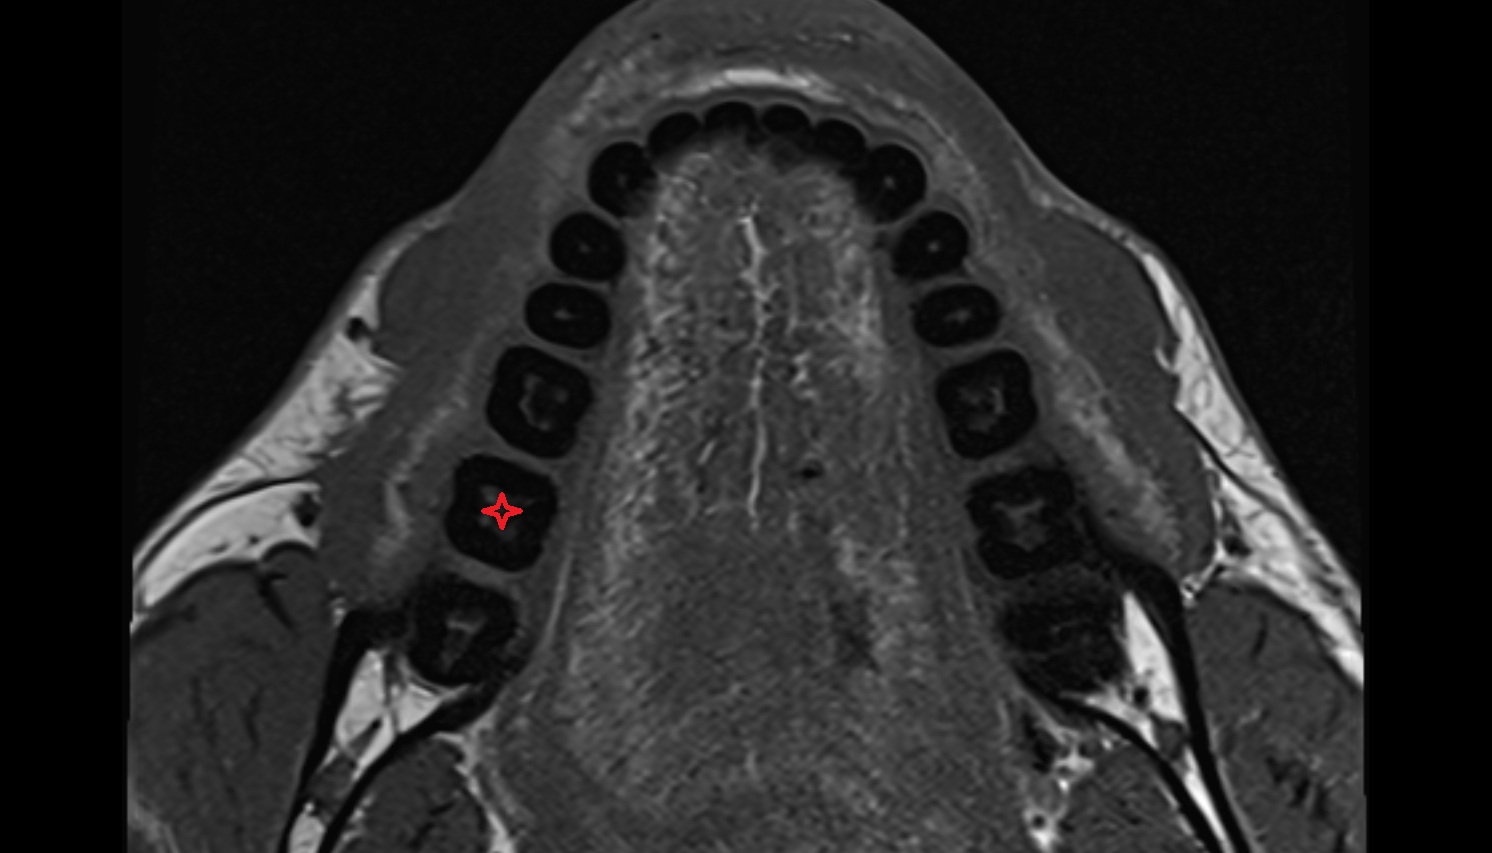

- Mandibular canal

- inferior alveolar artery

- Inferior alveolar nerve

- Inferior canine tooth

- Inferior first premolar tooth

- Inferior second molar tooth

- Inferior second premolar tooth

- Inferior third molar tooth

- Lateral inferior incisor tooth

- Root of lower molar tooth

- Lower molar apical foramen

- Enamel of lower molar tooth

- Dental pulp of lower molar tooth

- Dental branches of inferior alveolar artery, vein, & nerve